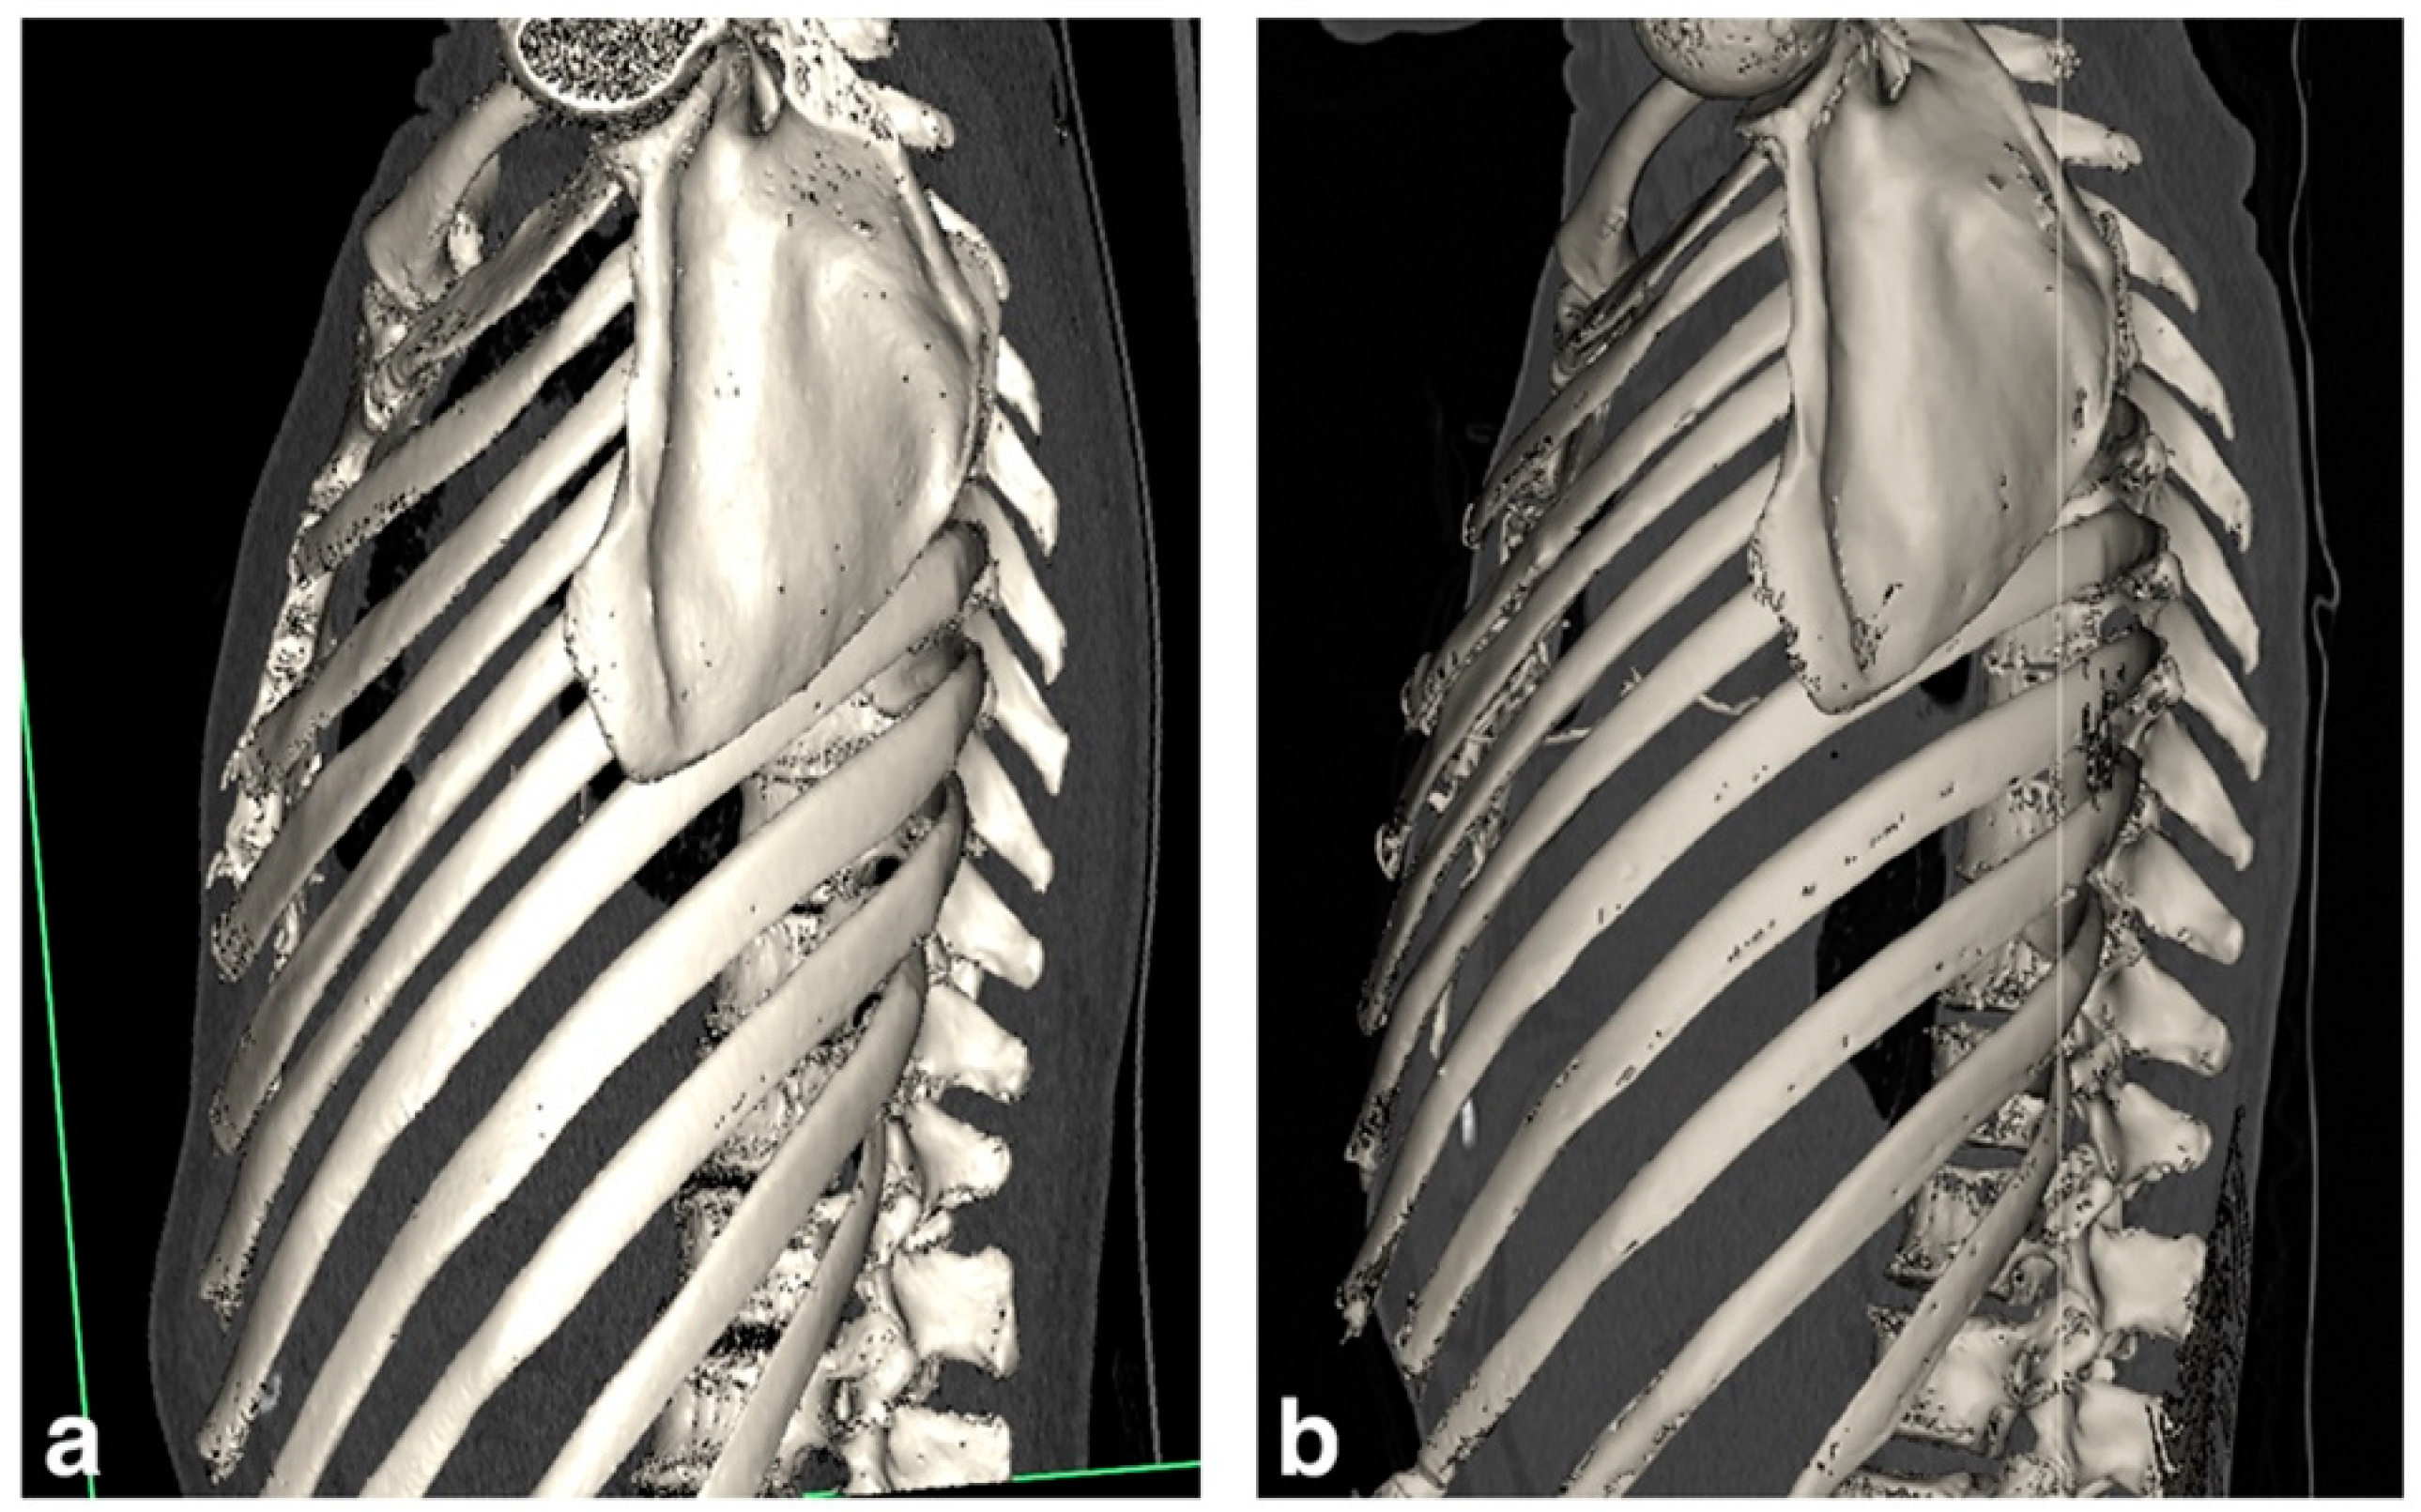

3.1.1. Patient 1

3.1.2. Patient 2